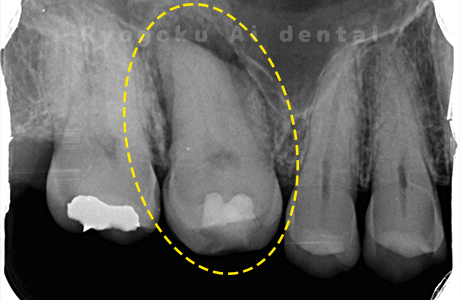

Case03

- 重度カリエス、慢性根尖性歯周炎

- 治療内容

- 自家歯牙移植

- 治療費用

- 220,000円

他院で右下の根の治療を行い、セラミックを被せる説明をされていたが、根の治療が終わらないため転院された患者さんです。隣の親知らずの抜歯の必要性と、根の治療を行なっている歯牙の予後が悪いため、移植治療を提案し、右下の親知らずの抜歯と同時に、右下の奥歯(7番)への移植治療を行いました。被せ物を行う必要もなく、順調に経過してます。

<リスク・副作用>

治療後、痛みや違和感、出血、腫れなどが出る事があります。喫煙者、糖尿病などの方の場合、歯が生着しない場合があります。